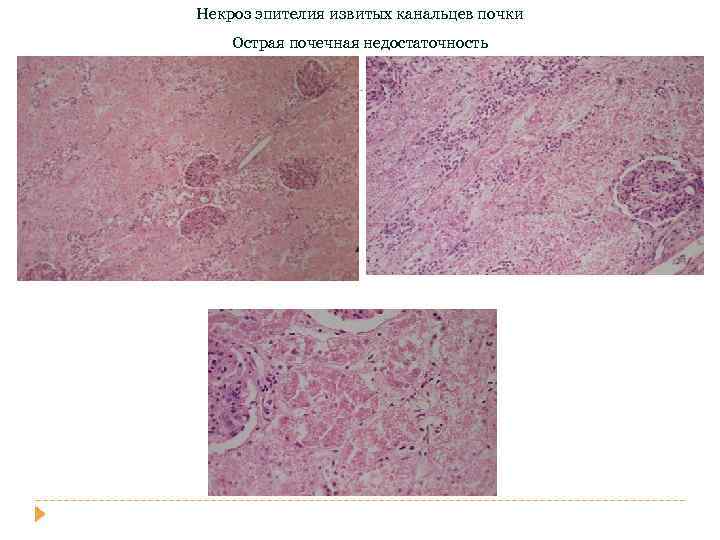

Некроз эпителия извитых канальцев почки Острая почечная недостаточность